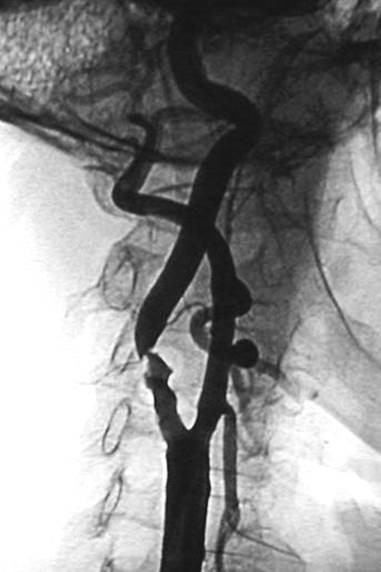

• Катетер проводят к сонной артерии под контролем рентгеновского излучения.

• Вводят контрастное вещество, чтобы увидеть артерию на экране.

• За место сужения хирург проводит устройство для предовращения миграции компонентов бляшки в сосуды головного мозга (церебральная протекция).

• Хирург устанавливает стент, который расширяет суженный участок.